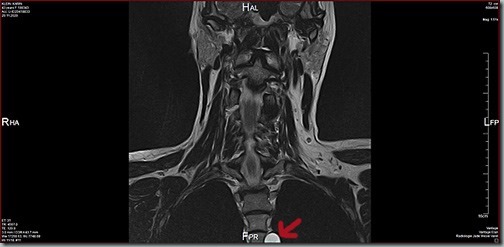

… hab ich heute keinen in meiner Neuro-Praxis, wahrscheinlich sind sie nicht da gewesen. Aber ich hab meine CDs durchgesucht, da war leider keine neuere BWS dabei. Also hab ich mir die HWS-Aufnahmen vorgenommen und siehe da: auf den Bildern von 11/2020 sieht man das Ding auch schon deutlich. Auf den Bildern von 2019 ist der Wirbel nur noch ansatzweise drauf, da kann man was erahnen, aber nicht sicher sehen. Und auf meinen BWS-Aufnahmen von 2016 war noch nichts zu erkennen.  Mal sehen, ob ich Montag jemanden in meiner Neuro-Praxis oder der Radiologie dran bekomme um zu erfahren, ob das Teil schon in dem Bericht von November erwähnt wird.

Nicht gerade klein, das gute Stück …